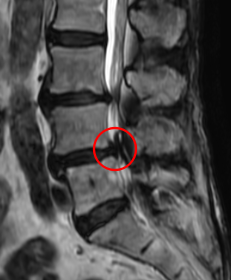

腰痛MRIを確認したところ、L3/4と、L4/5の2か所に腰椎すべり症が原因とみられる脊柱管狭窄症を認めました。L4/5は特に狭窄が酷くなっていました。

痛みの原因は2か所の狭窄だと考えられます。